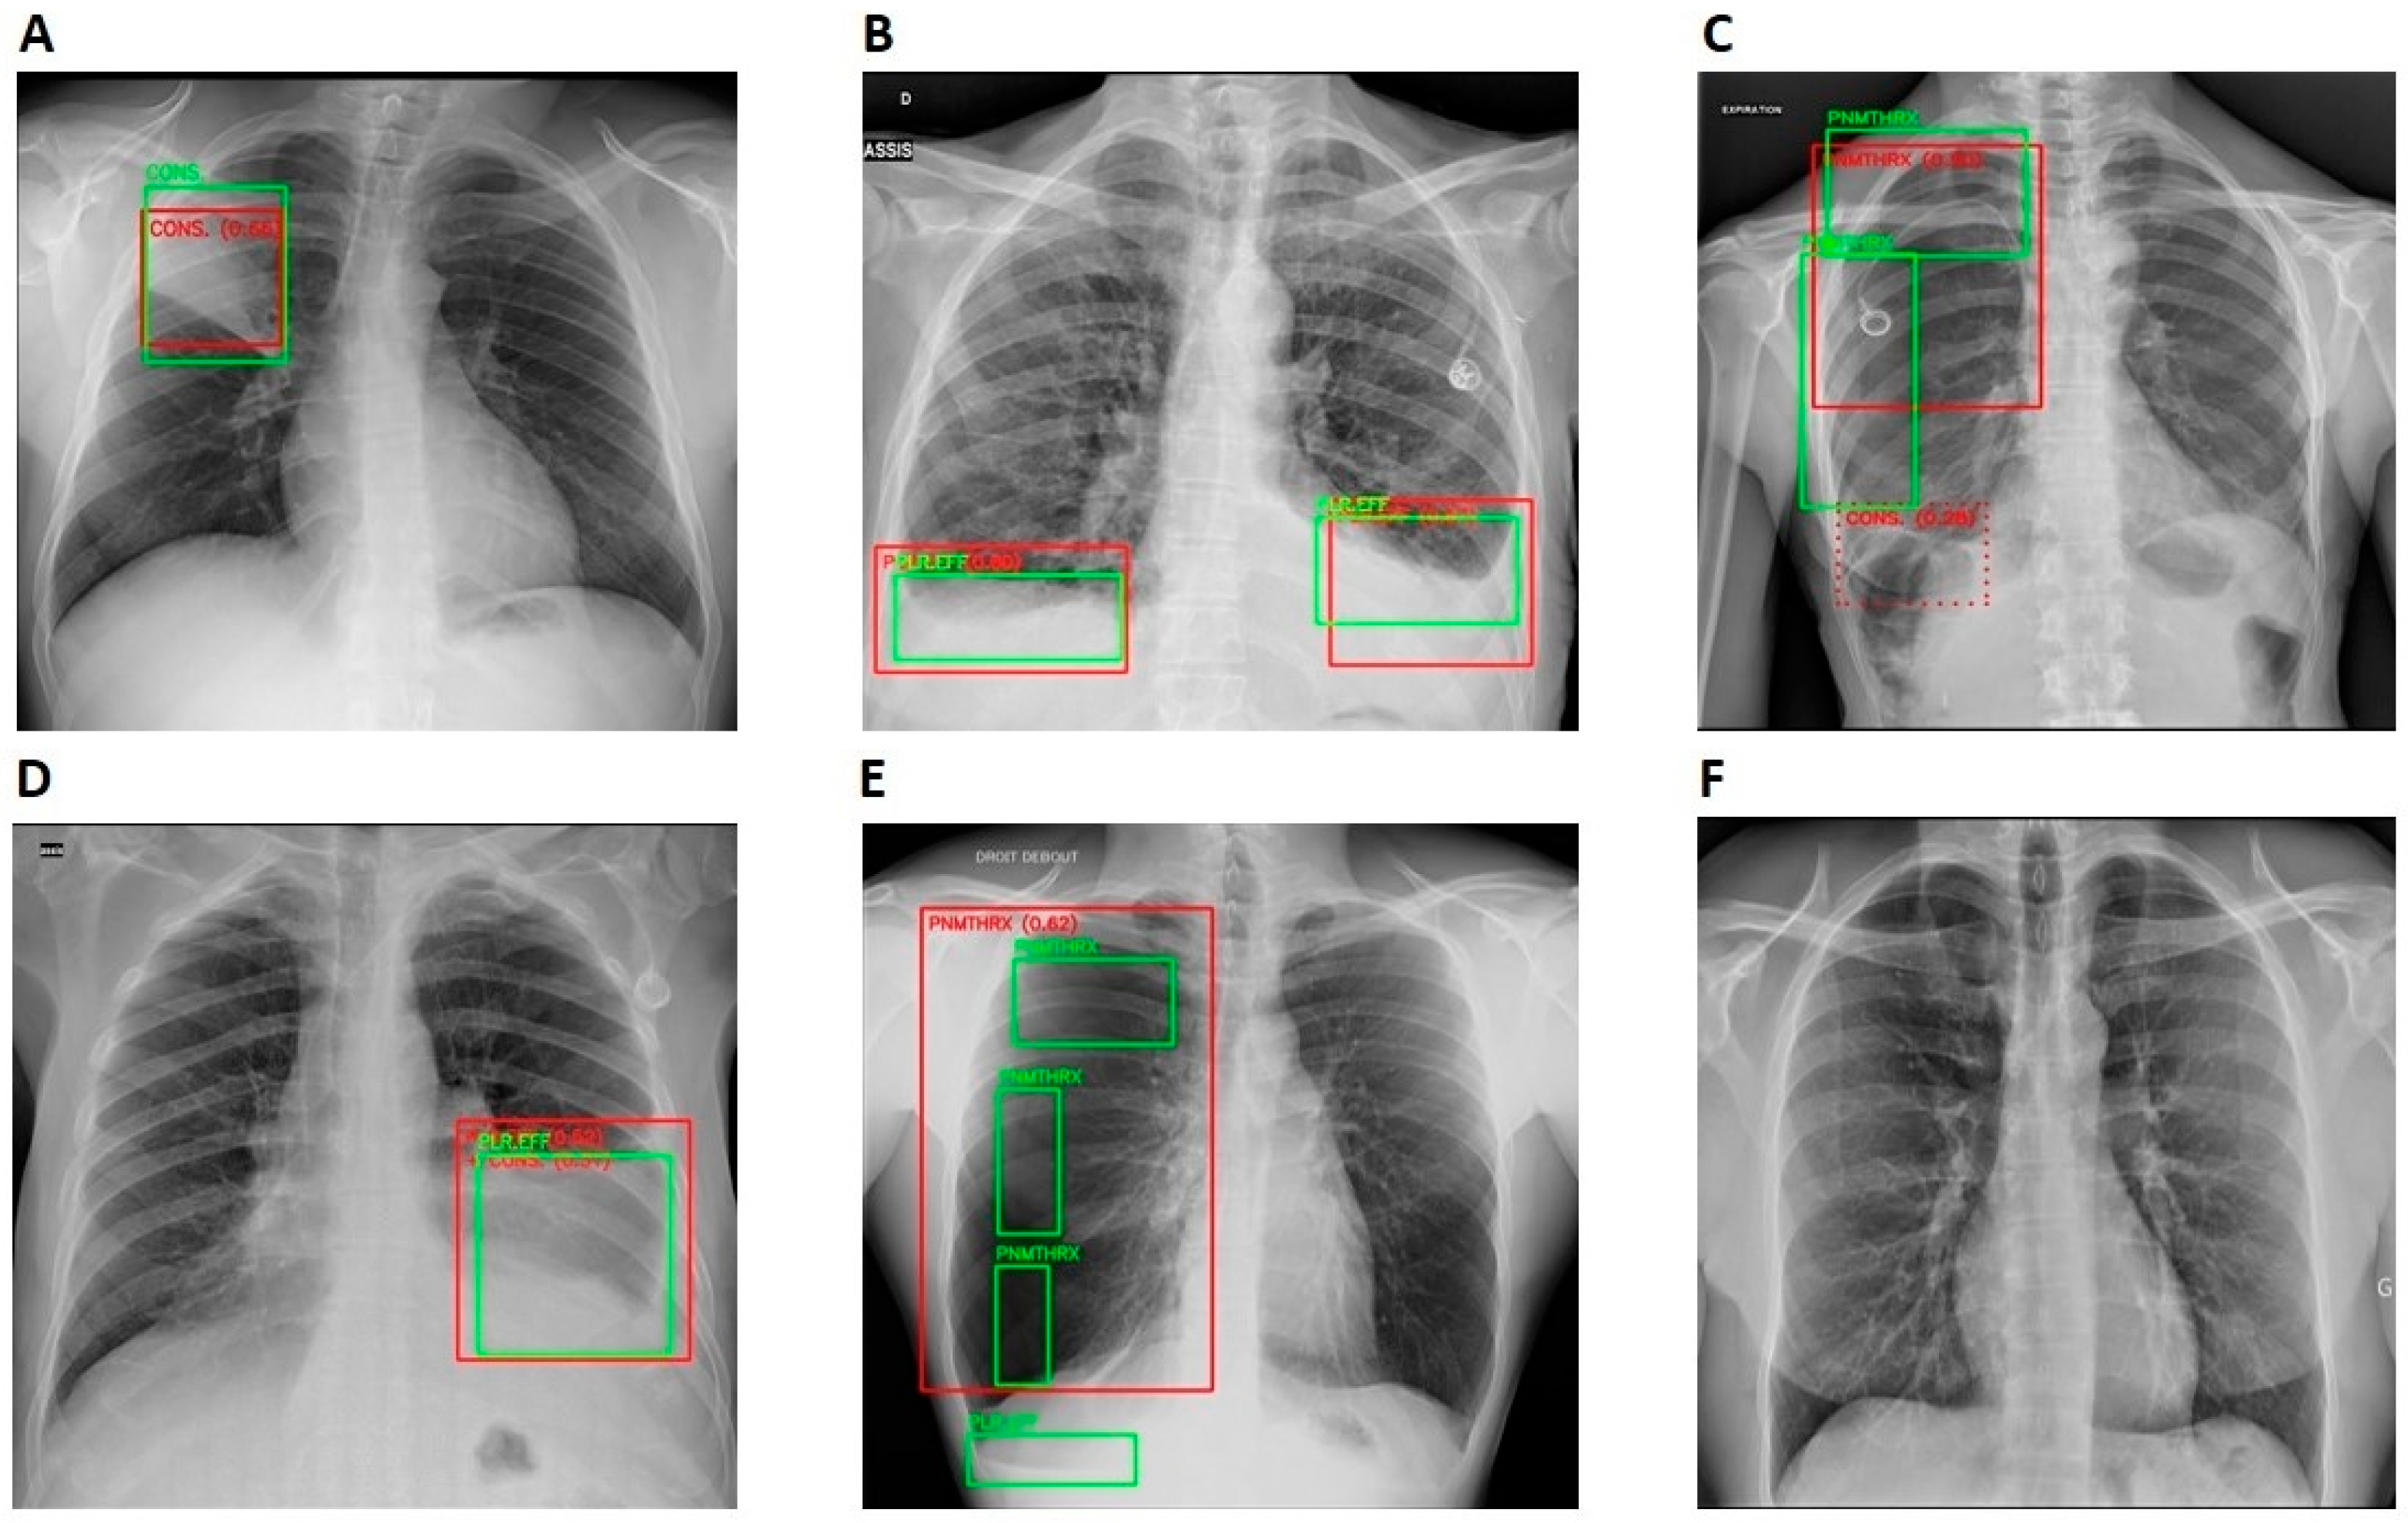

The AI model achieved an average sensitivity, specificity, and PPV and NPV of 0.964, 0.844, 0.757, and 0.9798, across all the centers, respectively. The highest false-positive rate (FPR) was observed in the nodules (20.1%), followed by the pneumothorax (18.8%) and the cardiomegaly (16.1%). Consolidation had the lowest FPR of 11.4% but the highest false-negative rate (FNR) of 7%, compared to other anomalies. Nodules had the lowest FNR of 1.2% followed by cardiomegaly (2.2%). The distribution of overlap of TP, TN, FP, and FN cases between Rayvolve and the reference standard is shown in Table 2. The performance metrics per anomaly are shown in Table 3. Examples of TP, TN, FP, and FN CXR studies are shown in Figure 4.

Figure 4.

Standalone performance of Rayvolve examples. Green and red boxes represent ground truths and the AI model predictions. (A) Rayvolve correctly identified consolidation (TP). (B) Rayvolve correctly identified pleural effusion (TP). (C) The AI model correctly identified pneumothorax on the right lung. However, it incorrectly detected consolidation on the right lung (TP for pneumothorax and FP for consolidation). (D) The AI model correctly identified pleural effusion on the left lung. However, it incorrectly detected consolidation on the left lung (TP for pleural effusion and FP for consolidation). (E) Rayvolve correctly identified pneumothorax. However, it missed pleural effusion on the right lung (TP for pneumothorax and FN for pleural effusion). (F) The AI model correctly identified a normal scan (TN).